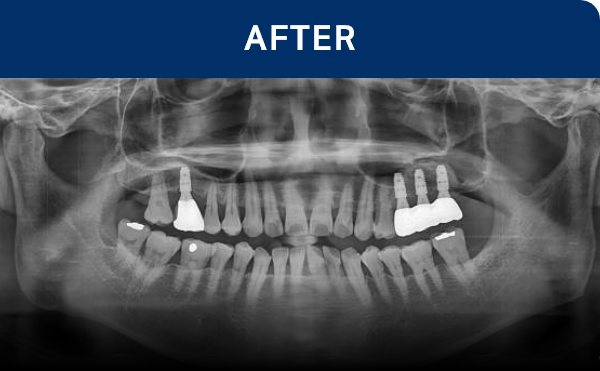

清晰可见的成果,

就是新吉种植牙

科值得信赖的证明.

通过种植牙, 让您无忧进食, 自在微笑, 重拾生活的舒适感